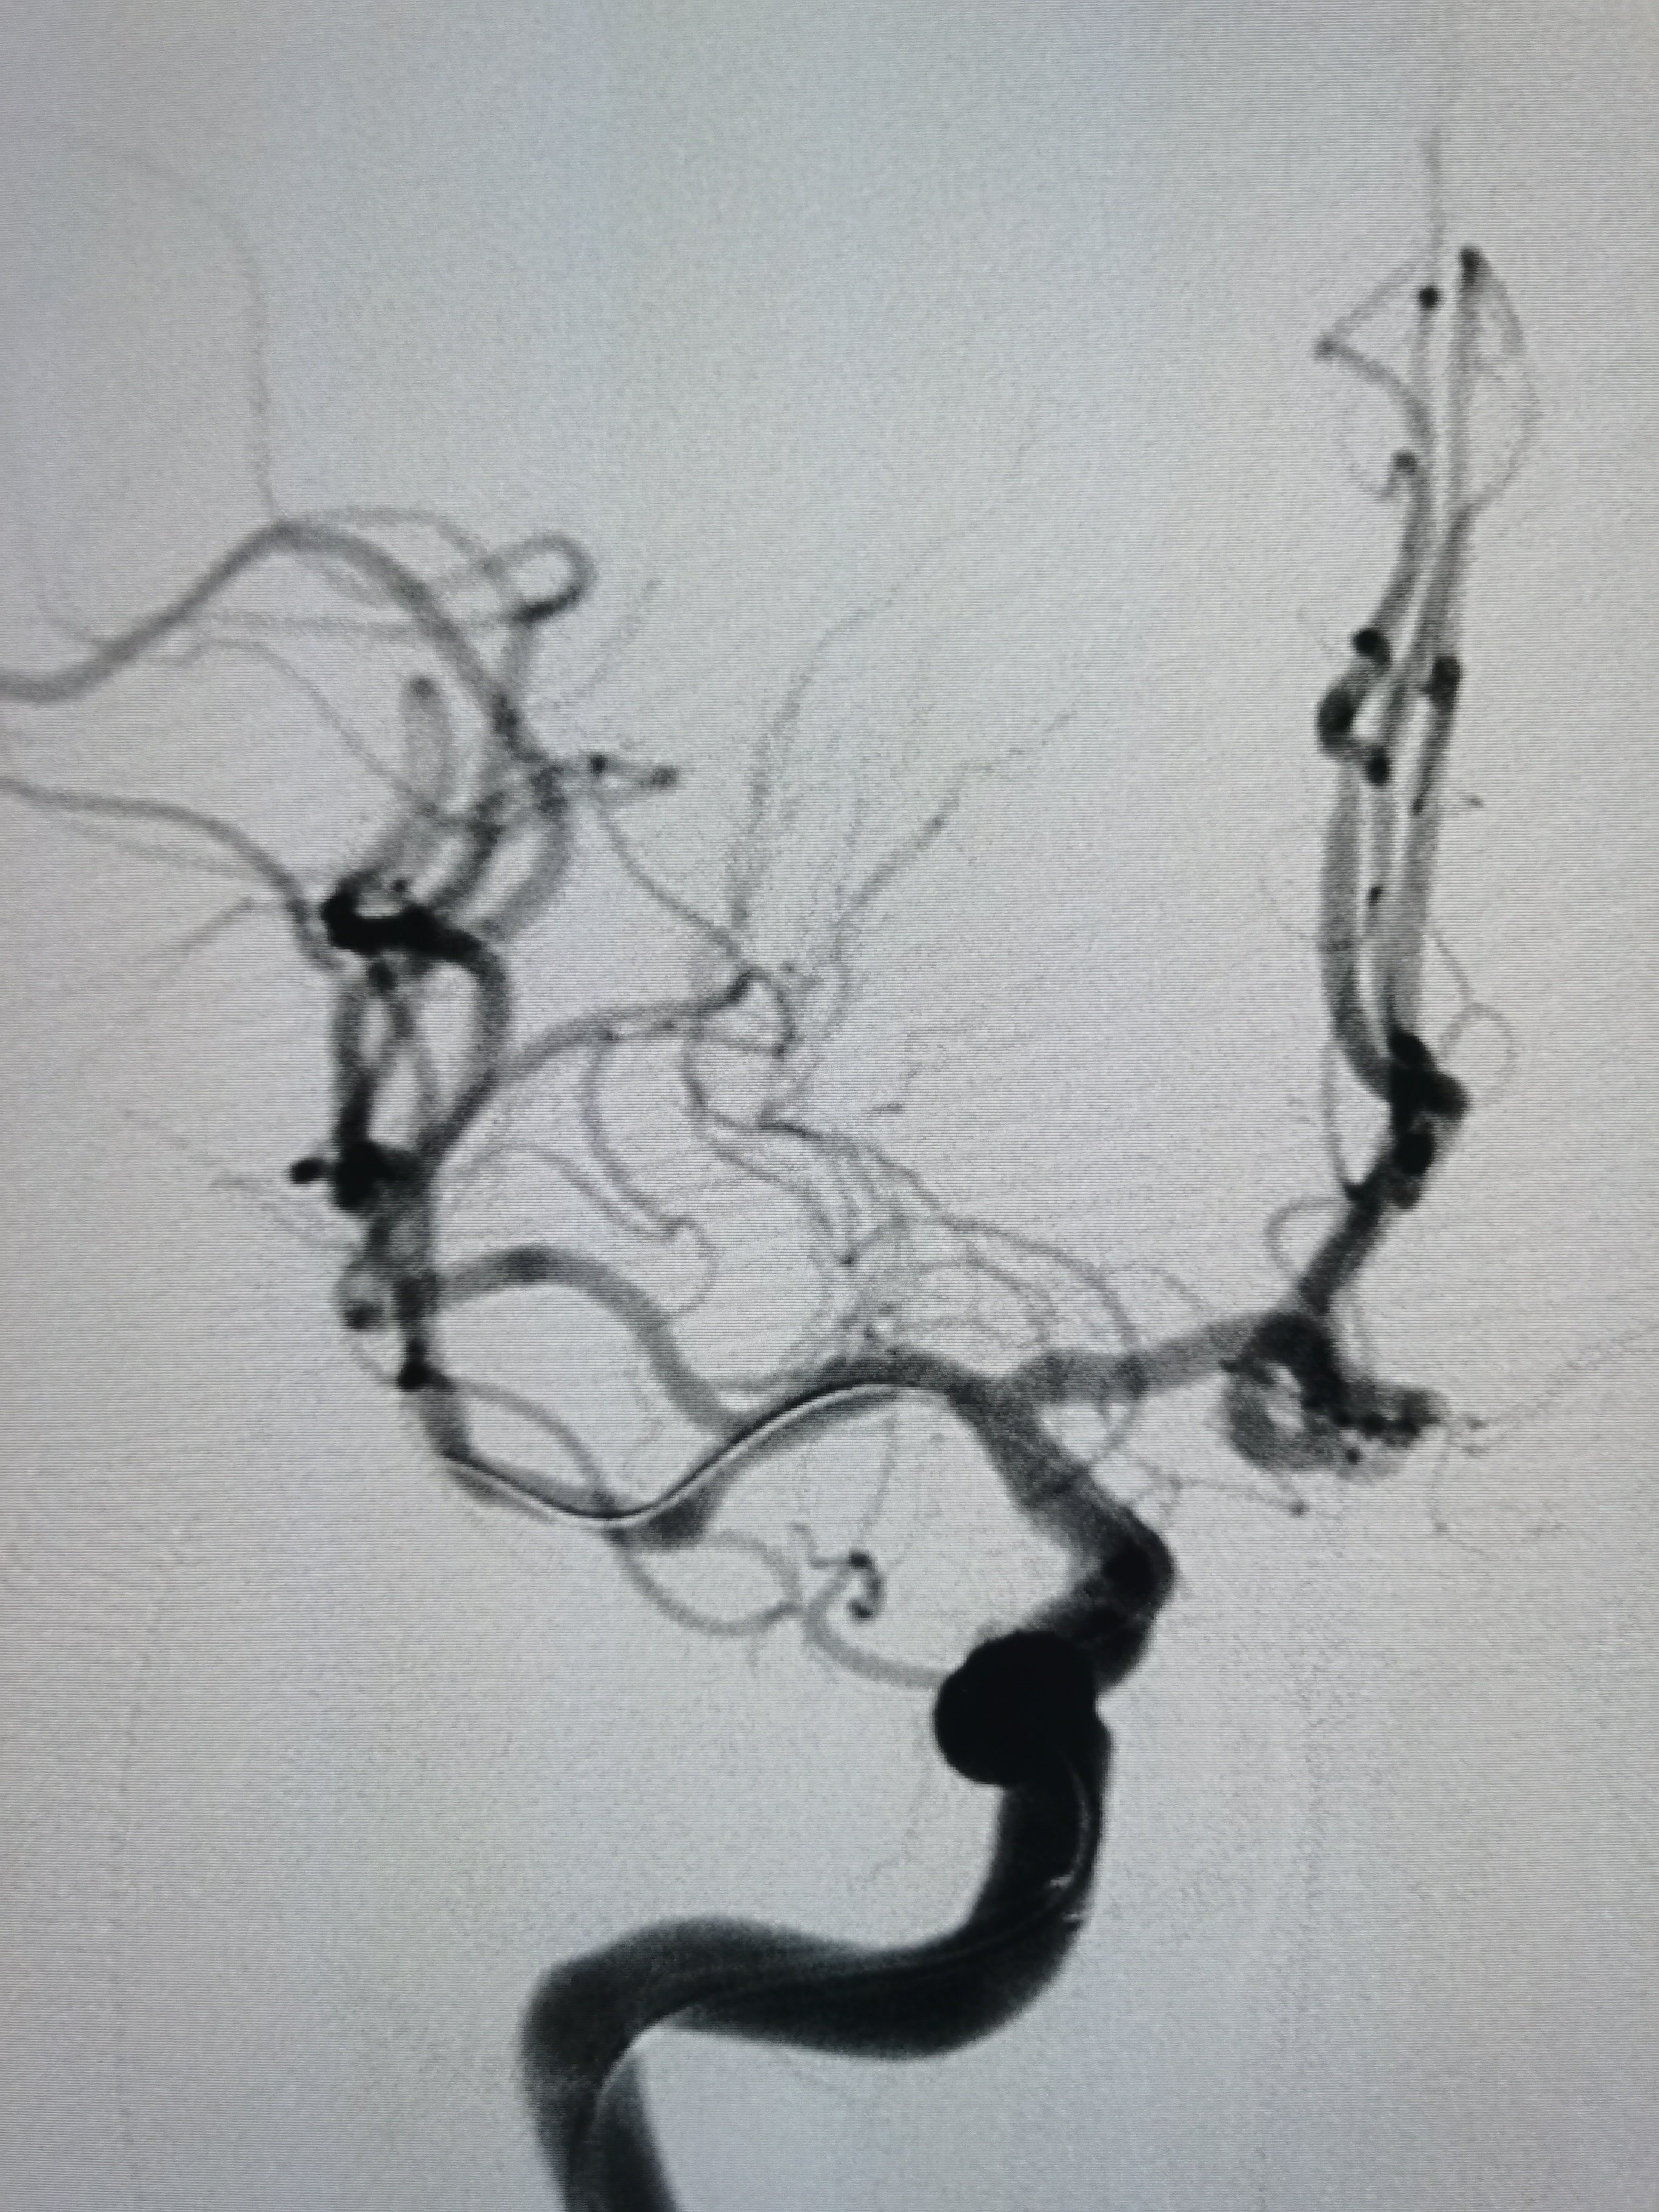

正位造影见狭窄解除,颅内血流通畅。

观察15分钟后造影未见明显弹性回缩。

侧位造影见颅内血流通畅。

球囊扩张后狭窄解除,决定不再植入支架,撤出导丝造影见血管通畅,遂逐级撤出各级导管,结束手术。